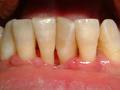

En el primer caso, se denomina gingivitis, a la inflamación de la encía generalmente causada por el acúmulo de placa bacteriana entre ésta y el diente. Normalmente ocurren cambios en cuanto a la forma, consistencia y coloración de la encía. Ésta se vuelve más grande, más hinchada y más rojiza por lo general, dejando a un lado el típico color rosa coral del tejido sano. Es muy frecuente que sangre al mínimo contacto, pero salvo casos puntuales, no suele producir grandes molestias para el paciente.

A diferencia de lo que ocurre en la enfermedad periodontal, en este caso no se afecta el hueso que sujeta el diente y es un proceso reversible, cuando se consigue mantener una higiene eficaz y eliminar la placa bacteriana del surco gingival, en el plazo de una semana aproximadamente el proceso va desapareciendo y el tejido vuelve a la normalidad. Unas encías sanas no deden sangrar.